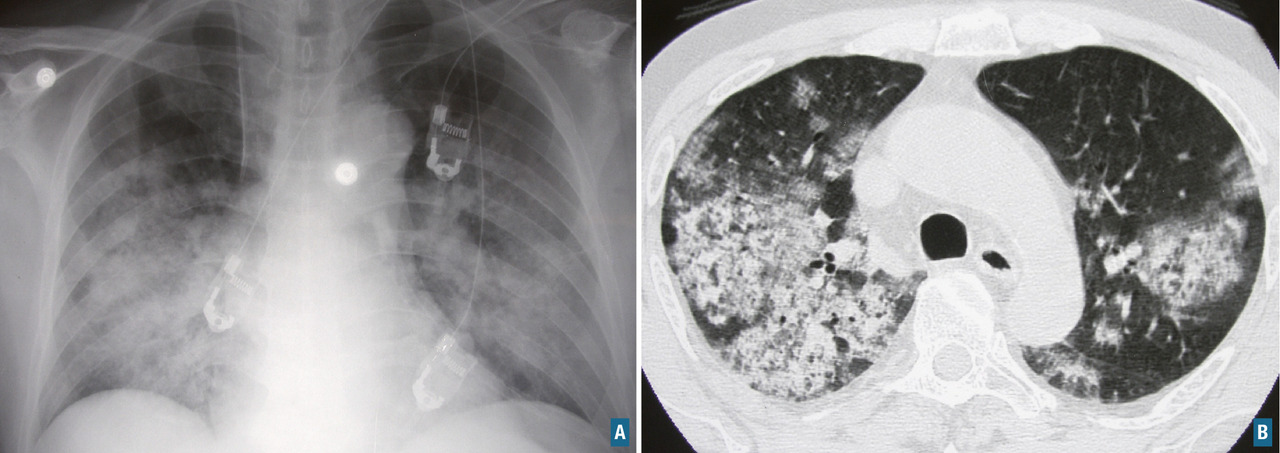

L’atteinte pulmonaire est variable : infiltrats alvéolaires, aspect en verre dépoli, nodules multiples excavés (fig. 9). L’hémorragie alvéolaire, complication majeure mais rare de la granulomatose avec polyangéite, se produit au niveau de la circulation pulmonaire distale entraînant un comblement alvéolaire (fig. 10). Elle se manifeste par une hémoptysie, une dyspnée, une anémie, des opacités diffuses alvéolaires et un liquide hémorragique au lavage bronchoalvéolaire (LBA). Des sténoses trachéo­bronchiques sont possibles.